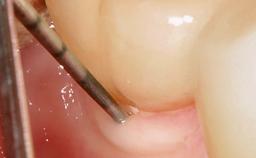

Peri-Implant Mucositis Treatment Outcomes on an Implant with a Submucosal Restoration Margin

Mauricio Araujo and Flauvia Matarazzo present this straightforward clinical case, demonstrating the potential effect of implant placement depth on the resolution of peri-implant treatment. A 42-year-old systemically healthy female patient, a non-smoker with no history of periodontitis, was treated at the Dental Clinic at the State University of Maringá, Brazil between 2008 and 2009, when she received five implants restored with single crowns at sites 14, 26, 27, 36, and 46. After delivery of the implant-supported prosthetic restorations, the patient was enrolled in the supportive peri-implant therapy (SPiT) maintenance program at the same university.